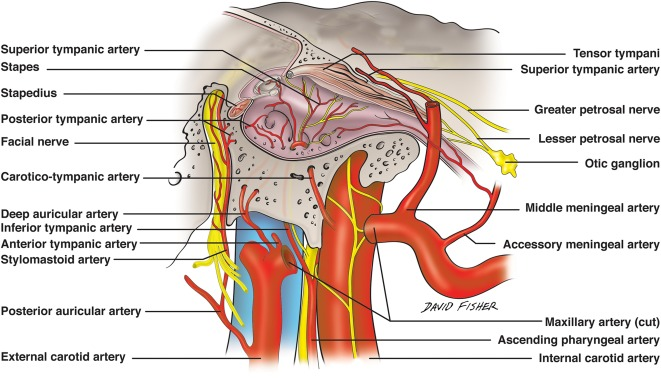

- Ant. tympanic a.

- 進入 tympanic cavity,供應 tympanic membrane

- Middle meningeal

- 被Auriculotemporal n. 環繞

Tympanic artery

- Auriculotemporal n.

- 夾 mid. meningeal a.

Temporal bone

- Carotid canal

- Ext. acoustic meatus

- Int. acoustic meatus

- CN VII, VIII

- Jugular foramen

- int. jugular v.

- CN IX, X, XI

- Stylomastoid foramen

- Foramen lacerum

- Petrotympanic fissure